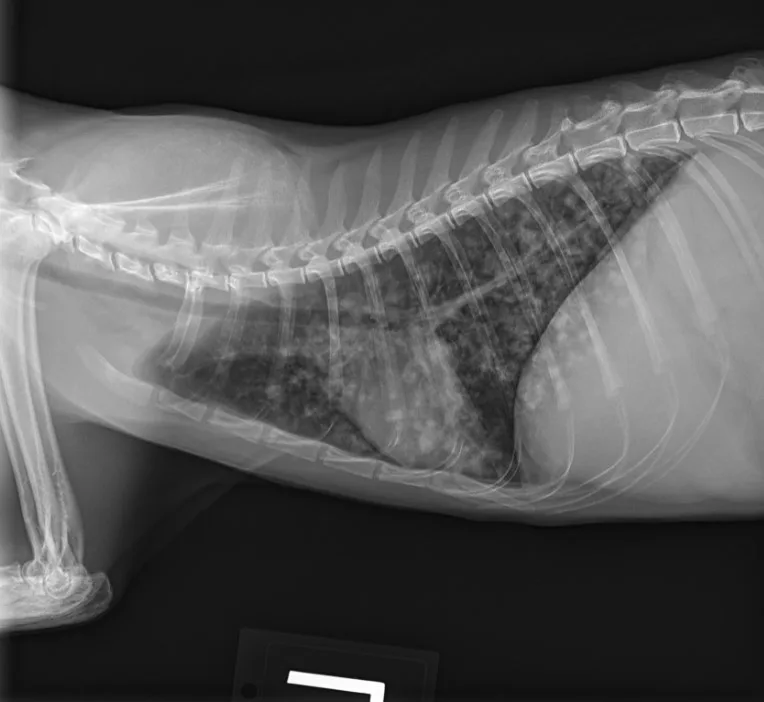

Clinical Image